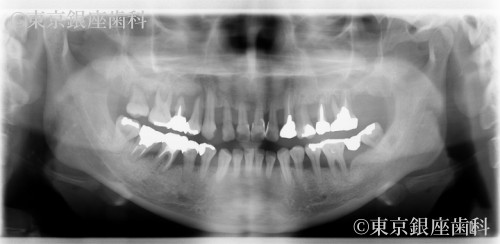

若くして重度歯周病に悩み上下インプラントで改善した40歳代女性の症例

Before

長年歯周病に悩み、不安を抱えて来院。上下インプラントで噛み合わせと見た目が改善。術後調整を経て安定し、現在もメンテナンス継続中。